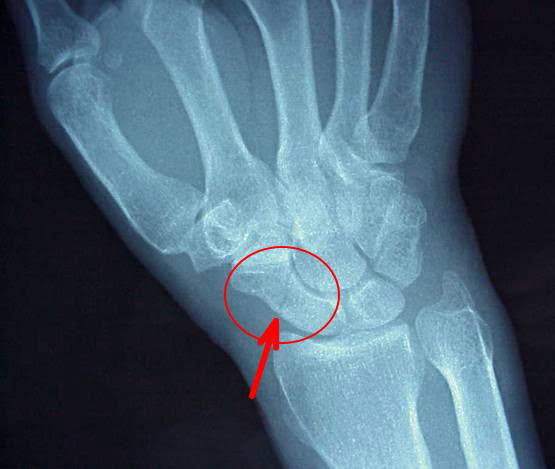

舟状骨は手関節にある8つの手根骨の1つで母指(親指)側にあり、手根骨の中でも重要な骨の1つで、船底のような彎曲をしているので船のような格好の骨ということで舟状骨と言います。

舟状骨骨折には、いろいろな折れ方があり、最も多い骨折部分は、舟状骨の腰部と呼ばれるくびれた部分です。舟状骨は、指先の側から手首に向かって血行があるので、腰部に骨折が生じるとその中枢側の血行不全が生じやすい為、偽関節になりやすいです。